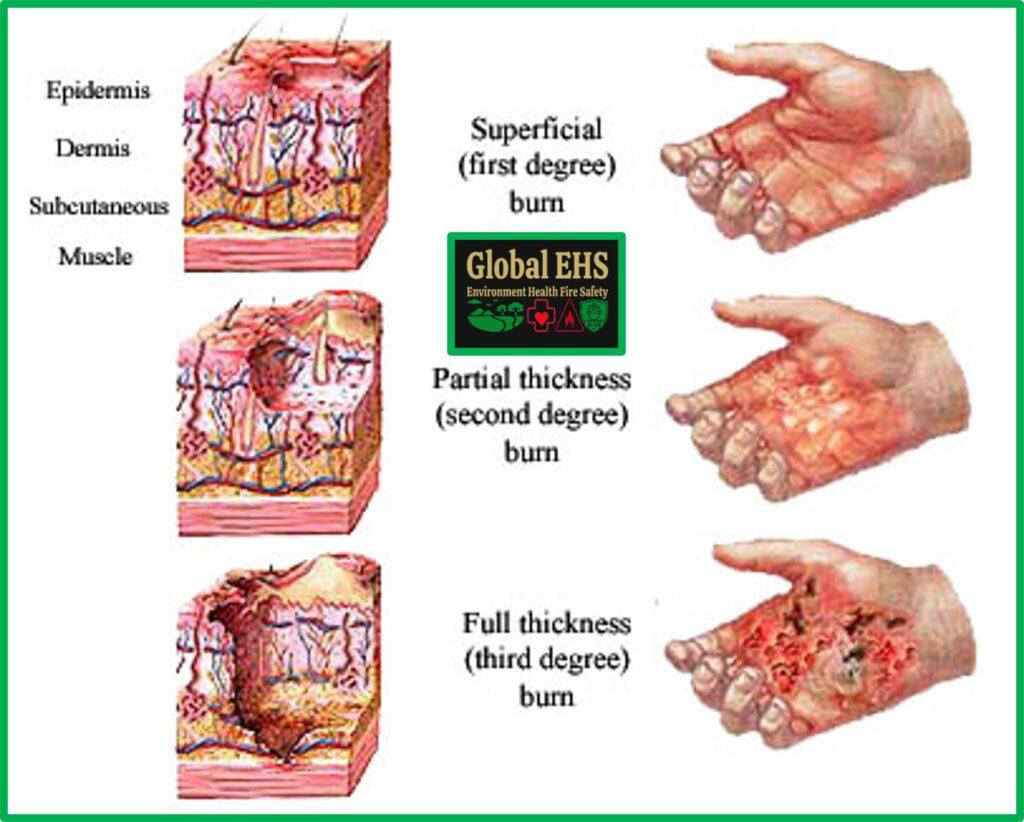

Burns First Aid Guide

https://globalehs.co.in/wp-content/uploads/2022/09/Classification-of-Burns-Degree-of-Burns-Global-EHS-1024x822.jpg

Medical Vector Illustration Burn Stages Degree Burns Of Skin 8910124

Leathery Skin After Burn

3 Astme P letus Mis See On Ravi Ja Paranemine SFOMC